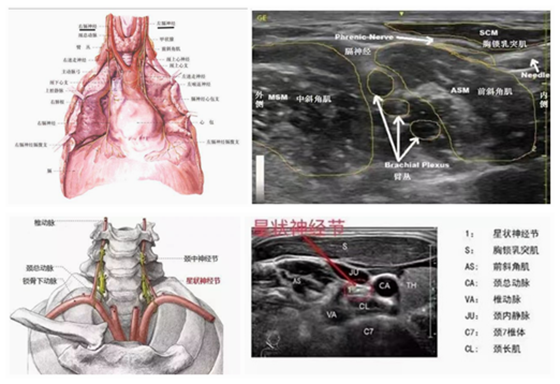

多种疾病都可能导致顽固性呃逆,如脑部的肿瘤、脑部的外伤、脑梗塞、脑出血、甲状腺病变、气管病变、肺部和心脏的疾病、胃肠道疾病以及过度焦虑等都可以诱发。而这位患者并不仅仅是胃着凉了,以前还有过脑梗史,目前还在口服抗结核药。前段时间还发现肠道肿瘤需要尽快手术,心情也非常焦虑,这些都是可能导致呃逆不能消除的重要原因。人体的膈肌分布在颈部和胸部两侧,只有双侧的膈肌都松弛下来,顽固性呃逆才能治好。打嗝也是机体对异常刺激的一种应急反应,交感系统的过度兴奋往往也是顽固性呃逆不能自行缓解的一个重要原因。因此,B超下膈神经与星状神经节阻滞治疗术对于顽固性呃逆有很好的治疗效果。

由于膈神经和星状神经节在人体的颈前部,此处密布丰富的动静脉血管及重要神经,还临近气管、甲状腺、肺部等重要器官,操作风险很大。随着医学影像学的快速发展,B超引导下膈神经与星状神经节阻滞术能够通过超声影像实时、动态地观察颈部内部组织结构,准确定位膈神经与星状神经节,提高治疗安全系数,大大降低了出现并发症的危险性。同时治疗药物准确的集中到需治疗的神经周围,往往也预示着更优的疗效。